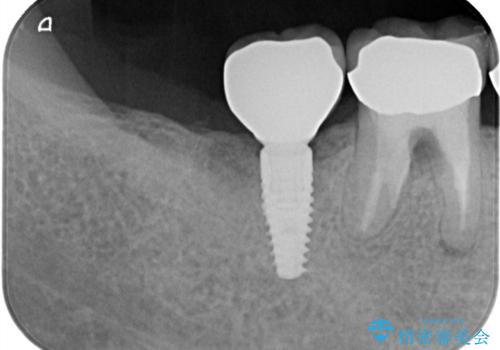

- 「他院で治療した被せ物が外れた」を主訴に来院された患者様です。診査診断を行い歯の保存が困難だったため抜歯後、インプラントで治療しました。

インプラントを入れるためには十分な骨の高さと幅が必要です。術前に検査を行い必要であれば別途、骨や角化歯肉を増やす治療も行う事があります。

インプラントの土台と被せ物は適合が良い物を制作するため、シリコン印象材を使用し型を取っています。